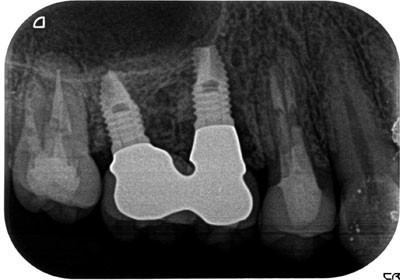

症例1

治療後

主訴 左上小臼歯から大臼歯部にかけて、脱離・歯冠崩壊、及び欠損があり、左奥では物が噛めない。

まだ年齢も50代と若く、義歯は煩わしく嫌であるという訴えがあり、左上5番・6番にインプラントを2本埋入する計画を立案。

副鼻腔までの距離がわずかしかないので、ソケットリフトと、骨の緻密化を計る為に、C・C・Wドリリング法を併用。

オぺから仮歯装着まで3ヶ月を要し、4ヶ月未満の治療期間を経て最終補綴物ジルコニア2本を装着。

リスクとしては、ソケットリフト(骨造成)による一過性の副鼻腔炎が起きる可能性がある。まれに洞底膜が破れる可能性がある。

ただし、膜は約3週で再生するので、膜の回復を待ち、再オペを行う。

費用 116万(オペ・ソケットリフト・人工骨・採血による濃縮血小板生成・仮歯・最終補綴物まで含む)